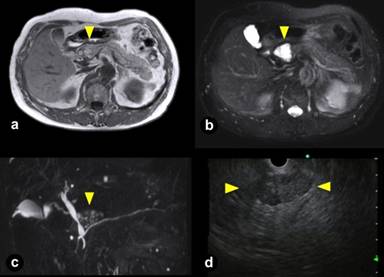

A 67-year-old Asian man with a medical history of lung cancer (well differentiated adenocarcinoma stage I) 14 years previously was followed up at our outpatient clinic after a right lower lobectomy. His serum HIV antibody was negative and there was no other significant medical history. A 20 mm mass in the body of the pancreas, which was a small cystic lesion in 2002, was clearly identified by CT scan and MRI in 2008, 2012, and 2013 respectively (Figures 1 and 2). Subsequent diagnosis of a serous adenoma based on diagnostic imaging and EUS-FNA had been obtained 2 years previously. However, there was a growing tendency, from 20 mm to 42 mm, over the 5-year period, and consequently we decided to resect the lesion. A transition of carcinogenic antigen 19-9 (CA 19-9) during this follow up period is illustrated in Figure 3. The intraoperative frozen section revealed a squamous-lined cyst accompanied by sebaceous glands without any malignant findings. Subsequently, resection of the cyst was performed. Chemical analysis of the cyst fluid was not performed due to an extremely small amount of fluid.

Figure 2. Magnetic resonance imaging (a., b., c.) and endoscopic ultrasonography (d.) of LECs with sebaceous glands in 2013. a. T1-weighted image revealed hypo- and hyper-intensity (yellow arrow head). b. T2-weighted image identified a hyper-intense polycystic lesion which protruded toward extra-pancreas (yellow arrow head). c. MRCP also revealed a polycystic lesion which resembled cheerios-like appearance (yellow arrow head). d. EUS revealed a solid-appearing lesion, measuring 4 cm, with slight posterior enhancement in the pancreatic head (between yellow arrow heads). |